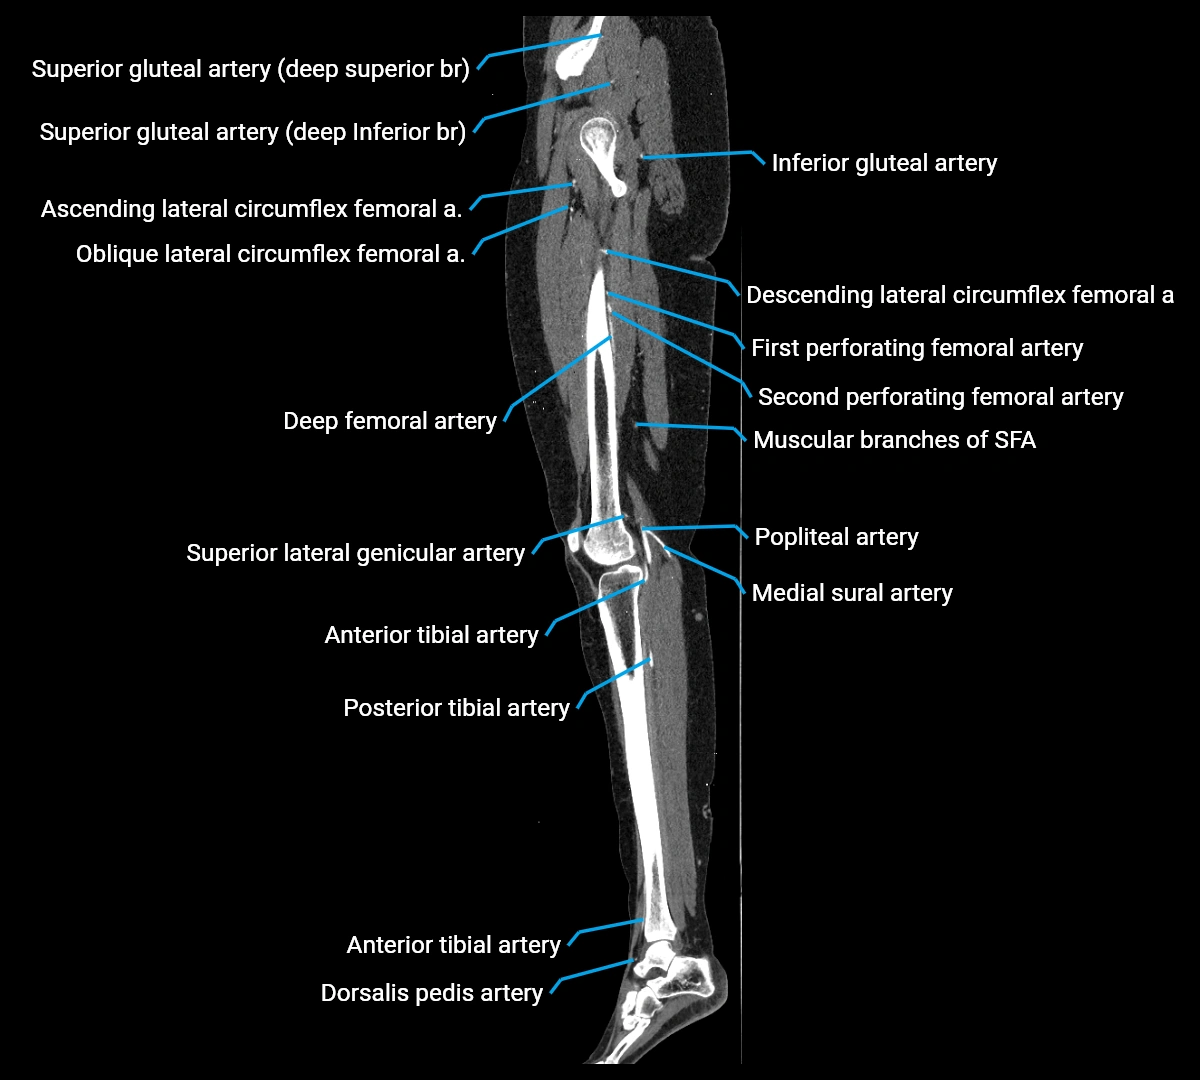

Contrast-enhanced CT (CTA):

• Gold standard for abdominal aortic imaging

• Provides excellent detail of lumen, wall, aneurysm, thrombus, and branch vessels

• Multiplanar and 3D reconstructions help in aneurysm measurement, stent graft planning, and dissection evaluation

• Detects acute rupture, traumatic injury, or occlusion with high sensitivity